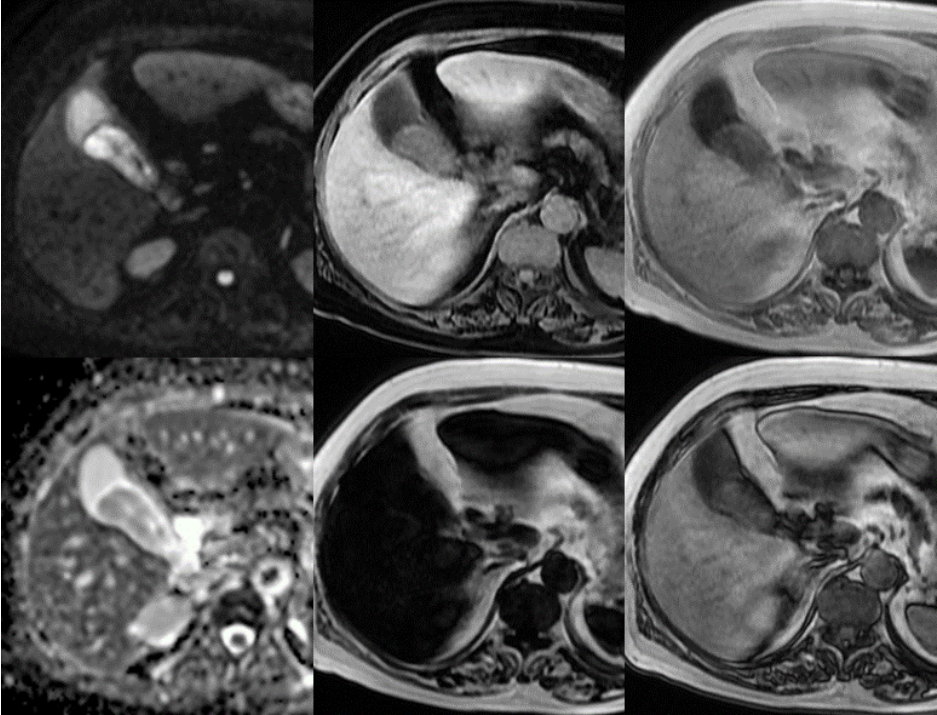

三、早上9:45,MR平扫 横断面脂肪抑制T2WI,胆囊内巨大等高信号影,占位性病变不除外。

冠状面T2WI 脂肪抑制 & 非脂肪抑制,貌似脂肪抑制前后,胆囊内病变无信号变化。

DWI胆囊内病变呈高信号,ADC值下降,提示弥散受限。 LAVA-FLEX四像图:水像病变呈等低信号,脂肪像低信号,同反相位未见显著信号改变,提示病变不含大量脂肪成分。 小朋友,你是否也有很多问号? 超声,CT都提示胆囊未见异常。 MR发现胆囊里面这么大一坨东西。 它是什么,它来自哪里,它会去向何方? 没有伪影的MR是不正常的,机器问题,参数问题? 四、晚上18点,超声复查